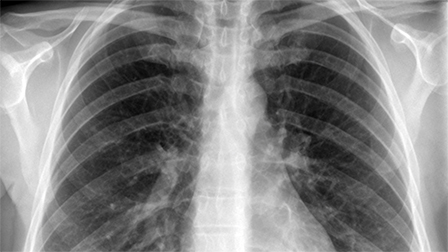

Hệ thống điện tử hỗ trợ chẩn đoán các bệnh hô hấp